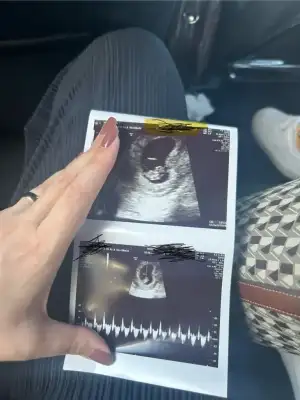

Çok geçmiş olsun canım

korkma hiçbirşey olmamıştır allahın izniyle arkadaşlarında dediği gibi kanama ağrı olmadıysa herşey yolundadır.